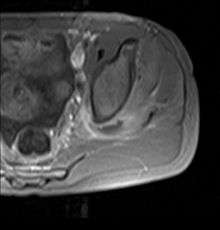

Axial T1 weighted fat suppressed post IV gadolinium contrast enhanced MRI image showing a mutliloculated bacterial abscess in the left gluteal muscle which grew Staphlococcus Aureus (methicillin sensitive) thought to be due to tropical pyomyositis.